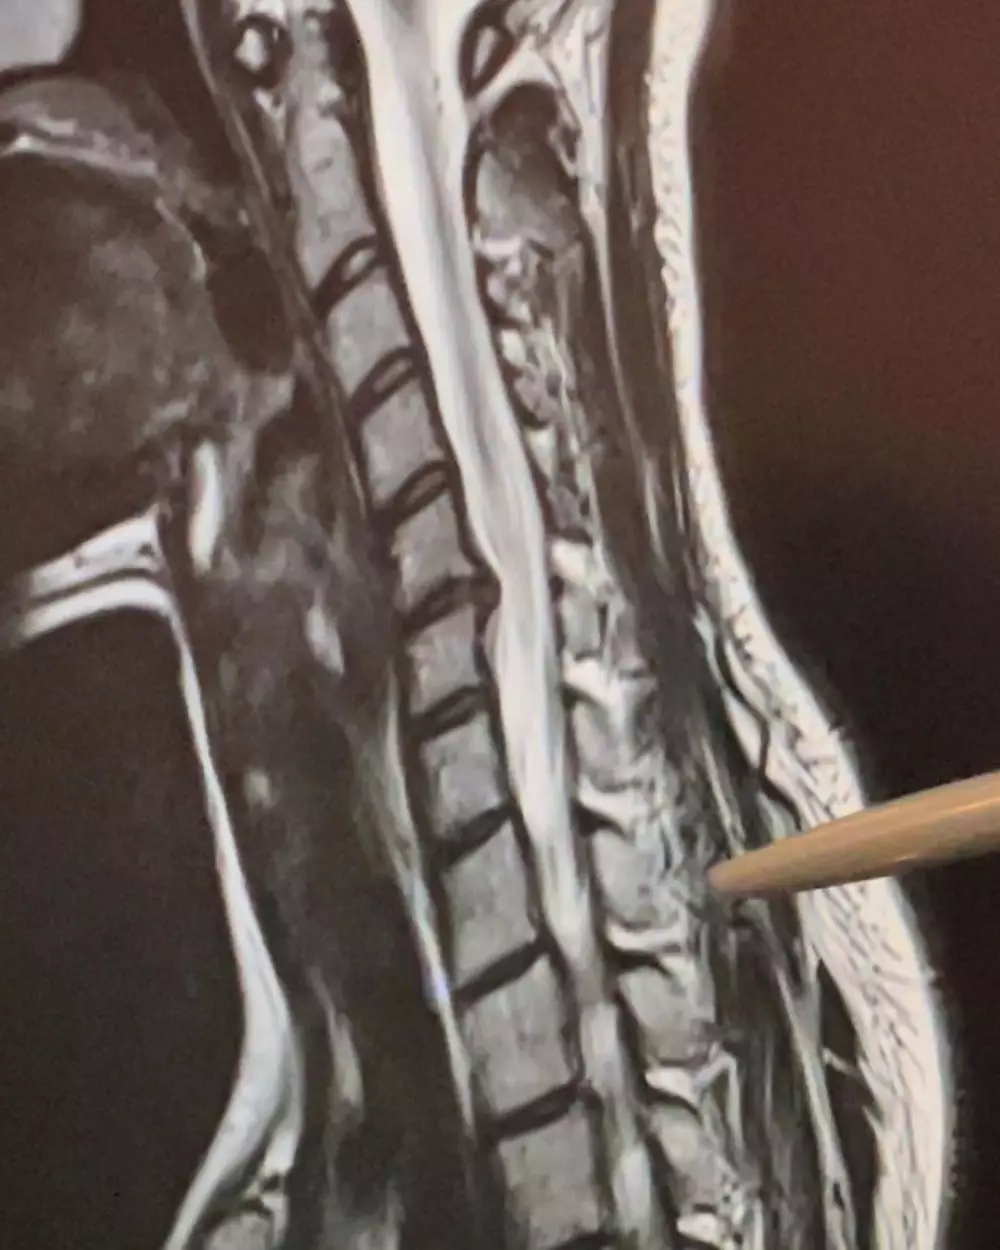

Brilio.net - Sheryl Sheinafia memberikan kondisinya terkini. Lewat unggahan Instagram pribadinya, perempuan berusia 25 tahun ini memberitahukan bahwa dirinya saat ini menderita saraf terjepit.

Dilansir brilio.net dari Instagram Sheryl, Kamis (10/1), Sheryl mengungkapkan bahwa awalnya merasakan sakit di bagian leher bahkan sampai ke lengan kanannya.

"Seminggu setelah ulang tahun, saya mengalami rasa sakit yang luar biasa dari leher dan lengan kanan," ujarnya dalam bahasa Inggris.

Kemudian rasa sakit semakin dirasakan Sheryl ketika dia melakukan kegiatan sehari-harinya.

"Sampai pada titik bermain gitar, menulis dan hanya duduk tanpa sandaran memberi saya masalah seperti sakit kepala dan mati rasa," sambungnya.

Tujuan Sheryl membagikan apa yang dideritanya saat ini sebagai bentuk pelajaran untuk yang lainnya agar lebih bisa berhati-hati. Karena disc herniation atau saraf terjepit tidak hanya dialami orang yang sudah tua atau lansia, namun juga bisa menyerang mereka yang masih muda.

"Disc herniation tidak hanya untuk orang tua," tutur Sheryl.

Sheryl juga menambahkan, agar orang-orang di luar sana tidak menganggap remeh saraf terjepit. Memang dampaknya begitu besar, bahkan menyebabkan kesulitan dalam berbagai hal bagi si penderita.